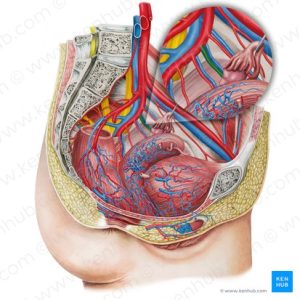

Imitsi y’amaras0 (uterine blood vessels)

Mu ibyara, imitsi y’amaraso igira uruhare mu gutanga oxygen n’ibindi bikenerwa ku myanya myibarukiro, ndetse no gufasha mu mikorere y’inyababyeyi. Iyo mitsi irimo:

– Imitsi mito (capillaries): niyo itanga amaraso ku bice byose bya nyababyeyi.

– Imitsi minini (arteries and veins): zifasha mu gutwara amaraso menshi, zigatanga imbaraga n’ibikenerwa mu gihe nyababyeyi ikora.

– Uterine arteries: imitsi itanga amaraso ku nyababyeyi, ikaba ingenzi cyane mu gihe cyo kubyara.

Imitsi y’amaraso rero ikorana n’imyanya myibarukiro kugira ngo ibyara rigende neza, ikanafasha mu kugabanya amaraso atakara cyane nyuma yo kubyara.

-IV-Ibyago mu ibyara

N’ubwo kubyara ari igikorwa gisanzwe mu buzima bw’umugore, hari igihe gishobora kuzamo ibyago (complications) bigatuma umubyeyi cyangwa umwana bahura n’ibibazo bikomeye. Ibyo byago bishobora kuba bifitanye isano n’imyanya myibarukiro, imitsi y’amaraso (uterine blood vessels), cyangwa imisemburo itari gukora neza.

1. Kuva cyane (Postpartum hemorrhage)

Ni ikibazo gikomeye aho umubyeyi atakaza amaraso menshi nyuma yo kubyara. Akenshi giterwa na nyababyeyi idakomeye (uterine atony), aho nyababyeyi inanirwa gukomera no kuzirika imitsi y’amaraso nyuma yo gusohora placenta. Ibi bishobora guterwa no kubyarira igihe kirekire kuba inda yari nini, cyangwa kuba umubyeyi yarabyaye inshuro nyinshi. Hari n’igihe placenta isigaye imbere cyangwa ikitandukanya kare, byose bikongera ibyago byo kuva.